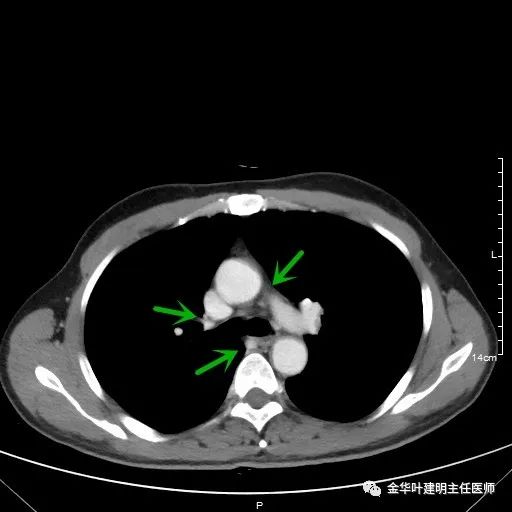

以上为纵隔窗,可见纵隔内未见显著增大的转移性淋巴结。